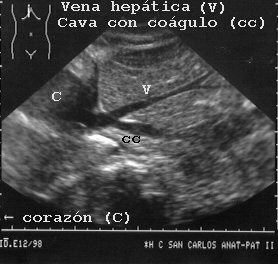

en la Fig 24 se ve un coágulo postmortem en la cava justo por debajo de la unión con la vena hepática.

24CAVACO.JPG (32209 bytes)

Fig 24